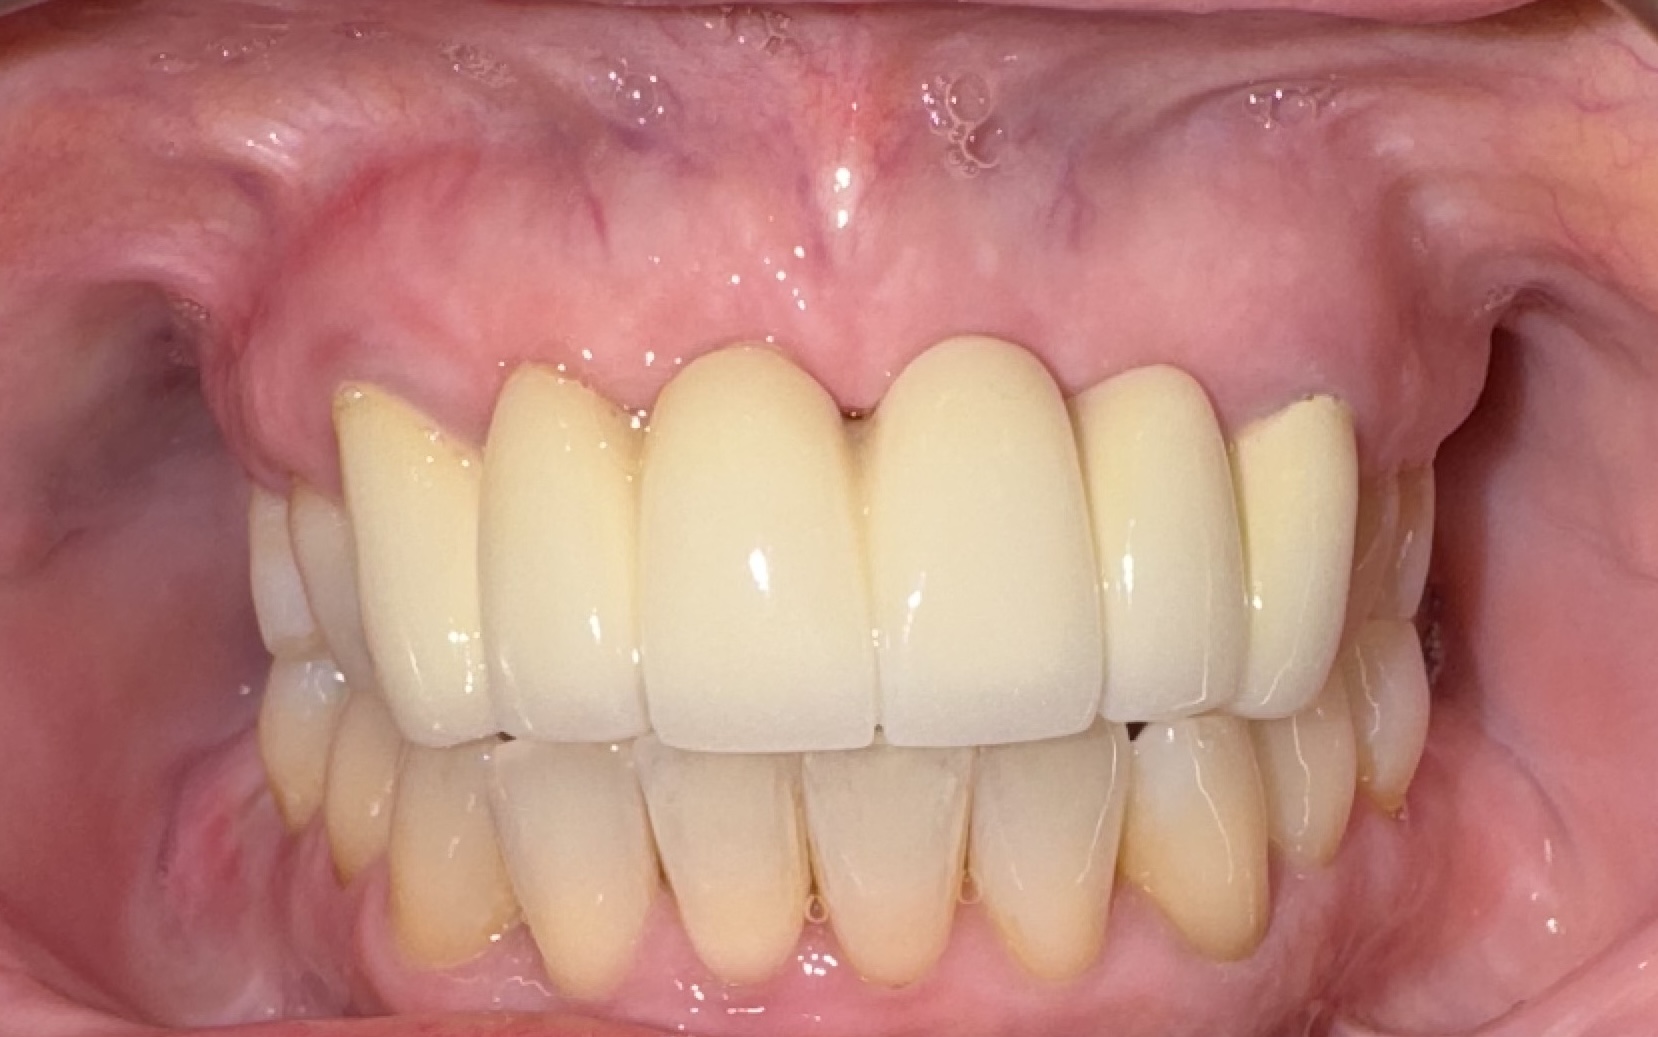

Visual Case Progression

All clinical images are shown at a consistent size for easy comparison.

Before & After (Groton Wellness Perio Protocol)

Patient Outcome

Roberta completed a structured, step-by-step plan addressing multiple areas of concern with surgical, periodontal, and implant phases. Treatment emphasized education, transparency, and biologically supportive healing protocols throughout a multi-visit journey.